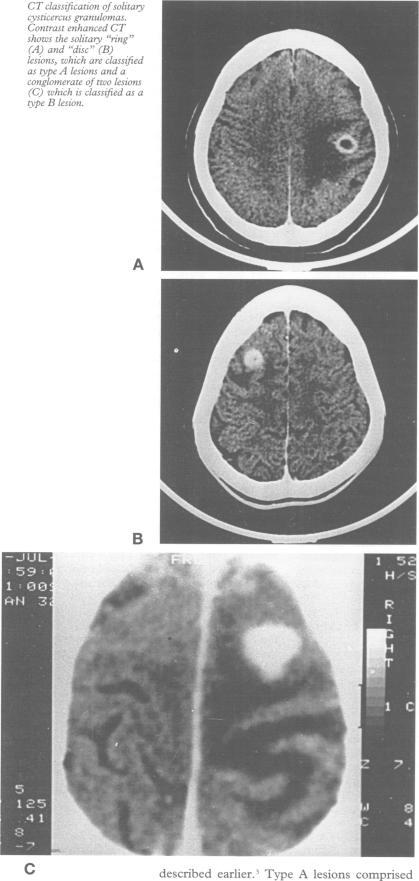

A study of the clinical, radiological, and pathological correlations in 43 patients with solitary cysticercus granuloma and epilepsy focused on factors that might help in predicting the presence of the parasite in the granuloma and those that might influence the formation of oedema around the granuloma. The duration of symptoms (< six months and > or = six months) and CT morphology of the granuloma (ring and disc, type A; nodular lesion, type B) were studied as factors that could possibly predict the presence of the parasite in the granuloma. The influence of sex of the patient and the presence of a neutrophilic response in the granuloma on the intensity of oedema around the lesion as seen on CT was also studied. The pathological features were studied in the excised granulomas. The intact or degenerated form of the cysticercus was evident in 22 of 43 specimens. Neither the duration of seizures (P = 0.17) nor the type of lesion on CT (P = 0.16) was predictive of the presence of the parasite in the granuloma. The sex of the patient (P = 0.51) and the neutrophilic response in the specimen (P = 0.73) did not correlate with the degree of oedema on CT indicating that neither of these host factors was a major determinant of oedema production. The findings point to the varied and unpredictable natural history of solitary cysticercus granulomas and the complex nature of host-parasite interactions in individual patients. The inability to predict the presence of the parasite in the granuloma on the basis of the clinical or radiological features precludes a selection of patients with such lesions for cysticidal drug treatment.